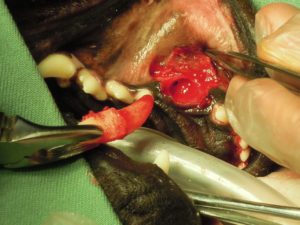

3.抜歯処置を希望されたため、歯肉を切開して

4.周囲の骨を削って

5.折れた歯を抜いて、周囲の骨をきれいにしてから